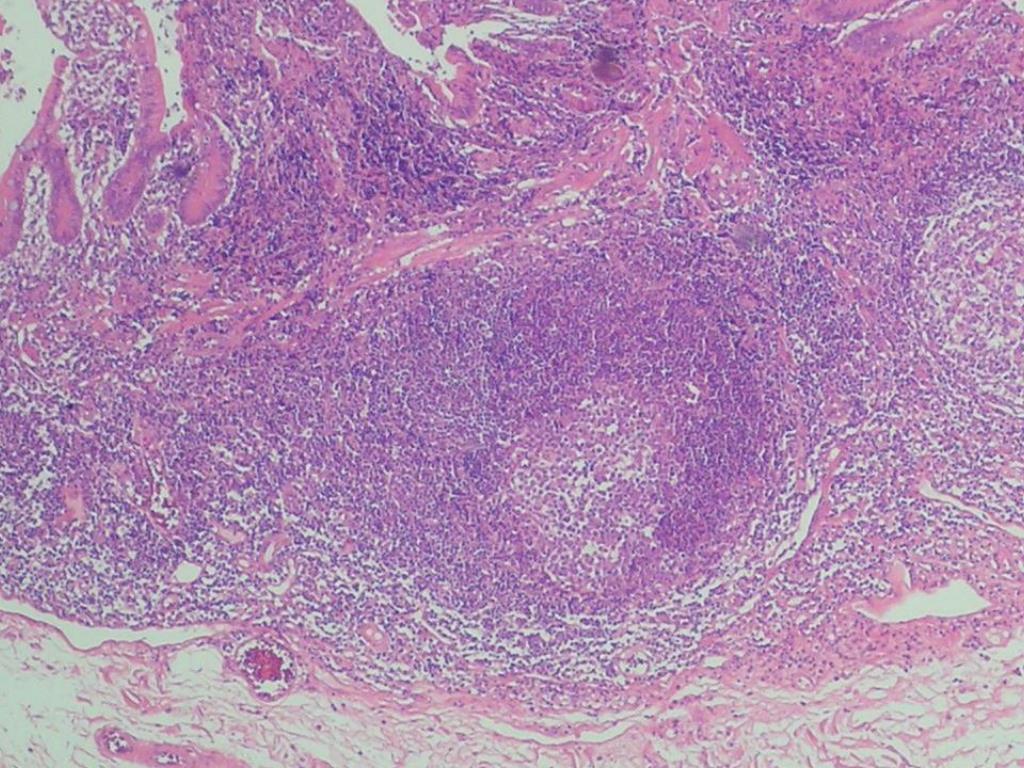

36. PATOLOGIA 外科医

41. PRODUCTO DE RESECCION INTESTINAL: APENDICITIS AGUDA FIBRINOPURULENTA, FIBROSIS PERIAPENDICULAR SEVERA. ILEON TERMINAL Y COLON CON HIPERPLASIA LINFOIDE FOLICULAR Y PERITONITIS AGUDA 外科医